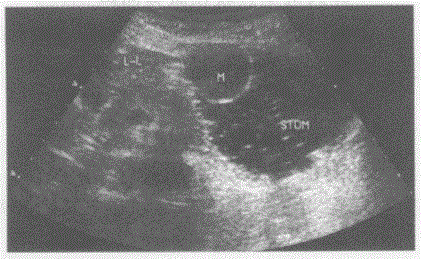

问题 临床资料:女,65岁,自述剑突下隐痛半年余。 超声综合描述:饮水500ml后超声检查,胃小弯处可见圆形低回声区,边界清晰,内回声均匀,向胃腔内突起,CDFI:周边可见环状血流信号。见下图及彩图。 {图1} 超声提示:

选项 A.肝癌(左叶) B.胃平滑肌瘤 C.胃内异物 D.胰尾实性占位

答案 B